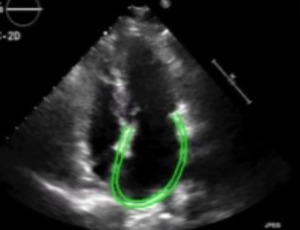

Myocardial work by 2 echocardiogram in different pathologies

Left ventricular performance has traditionally been evaluated by calculating ejection fraction (LVEF), however, the estimation of this by two-dimensional echocardiogram is subject to several limitations. On the other hand, speckle-tracking echocardiography (STE) with global longitudinal deformation (GLS) is increasingly used to assess even subtle myocardial dysfunction, although it is a well-validated method for clinical utility in the assessment of cardiac diseases, it remains limited by its load dependency [1,2].

Int J Cardiol Cardiovasc Dis, 2023, Volume Volume 3, Issue Issue 1, p23-28 | DOI: 10.46439/cardiology.3.027